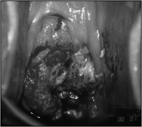

根治性子宮切除樣本

(子宮、子宮旁組織、部份陰道、骨盆腔淋巴結)

一般子宮頸癌隨著侵犯的程度,手術種類及範圍亦隨之不同,但手術範圍越大,手術中出血量及併發症也會增加。因根治性子宮切除,需切斷骨盆腔內許多血管、韌帶及神經,會切除一部份的陰道,故供應直腸、膀胱之神經血管會受到傷害,因而患者的小便及大便的功能也會在手術後受到不同程度的影響,但這一切都是為了能儘量完全切除惡性腫瘤,以避免復發及延長生命,不得不付出的代價。目前在根治性子宮切除,雖已有使用腹腔鏡操作,但對於腹腔鏡操作手術之惡性腫瘤轉移至腹腔鏡傷口及較大惡性腫瘤切除範圍是否足夠,仍需特別注意。至於神經保留式之根治性子宮切除,雖可減少術後膀胱及直腸功能發生的改變,但對於較大惡性腫瘤,可能造成手術切除範圍不夠,容易有癌症復發之問題。